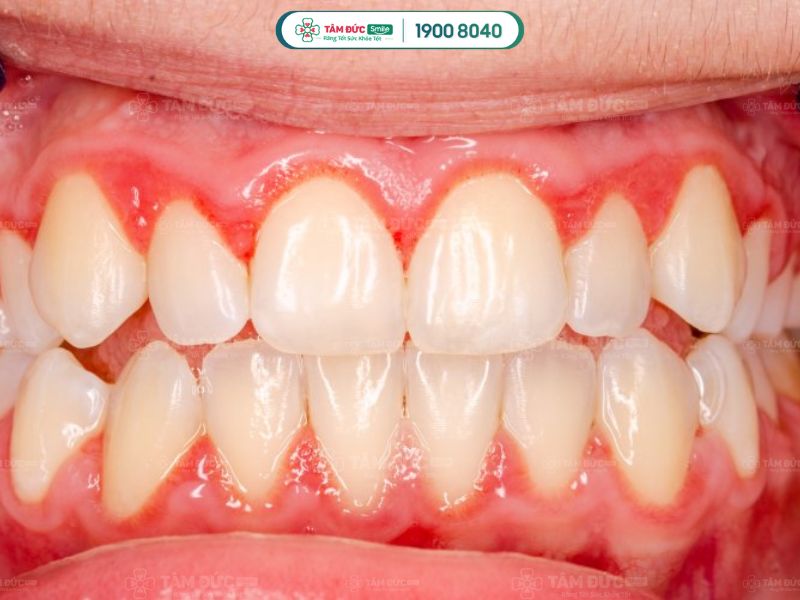

2.2. Viêm lợi

Không đánh răng trước khi đi ngủ lâu ngày tạo điều kiện cho mảng bám tích tụ quanh chân răng. Từ đó, vi khuẩn gây tổn thương lợi, làm chảy máu và sưng đau. Nếu không được chăm sóc và điều trị kịp thời có thể dẫn tới nguy cơ tụt lợi, răng lung lay.

không đánh răng dẫn đến viêm lợi

Không đánh răng đều đặn dẫn đến viêm lợi